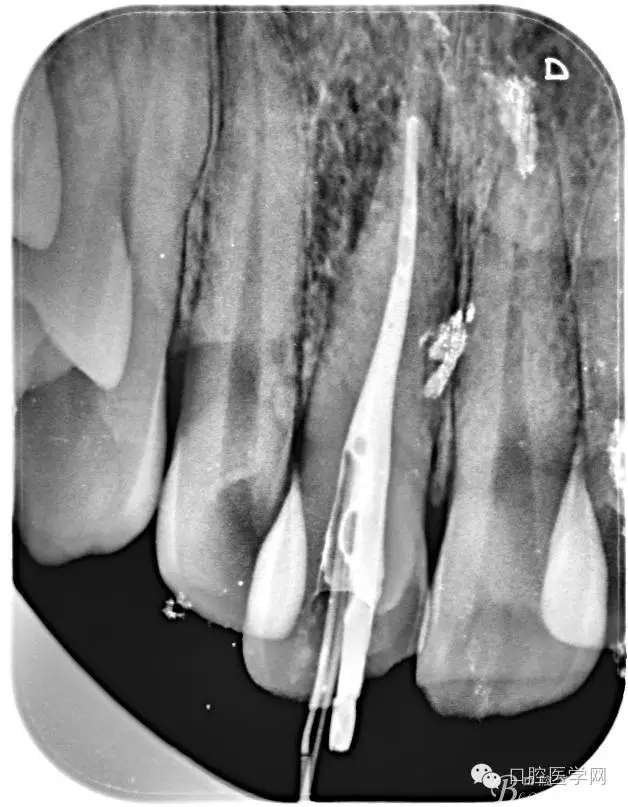

根管的解剖界限是从髓室根管入口到根尖部牙本质- 牙骨质交界处(生理性根尖孔) 。理想的根管充填应该是对生理性根尖孔冠方以上进行严密的三维封闭。临床上根据X线牙片判断根管充填的质量。牙片上充填材料与根管壁紧密接触一般被认为充填严密。关于充填止点,由于牙本质- 牙骨质界离根尖孔外表面平均距离为0. 5~0. 7 mm,同时相当多的根尖开口并不位于X线片的根尖处。因此临床上认为材料充填至距X线片牙根最尖端0. 5~1 mm (也有认为0. 5~2mm)为适填。

为达到更为理想的根充效果,研究人员和牙髓病医生一直在探索根管充填技术,并且发展出多种可供选择的方法。Ingle]将其归纳为3 类: ①“牙胶尖+封闭剂”式; ②“根尖1 /3充填”式; ③“注射或螺旋充填”式。目前临床广泛采用的主要是“牙胶尖+封闭剂”方式。按照充填压力的方向(侧向或垂直)不同和牙胶温度(冷或热)不同,根管充填有2 种基本技术:冷牙胶侧方加压充填和热牙胶垂直加压充填。现有的各种充填方法均是这2 种基本方法基础上的发展或改良。医生可根据方法的优缺点以及个人习惯选择使用。

6、封闭剂使用